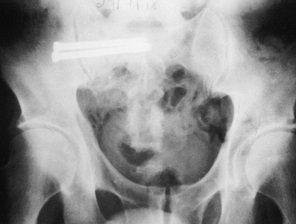

joint plate that we use to hold the reduced sacroiliac joint after

fresh pelvic fractures (Fig. 28.2) (14). We also use this plate to stabilize sacroiliac nonunions (Fig. 28.3, Fig. 28.4, Fig. 28.5, Fig. 28.6 and Fig. 28.7).

Figure 28.4.

A 45-year-old woman with a very painful nonunion of the sacroiliac joint on the left plus symphyseal diastasis. Her initial fixation, months ago, was with an external fixator. Of note, she also had a nonunion of the tibia on the left and an L-5 nerve root deficit. |

![]() |

Figure 28.5. Three-dimensional reconstructions from CT scans demonstrating the pathology present in Figure 28.4.

|

Figure 28.6. Three-dimensional reconstructions from X ray demonstrating the pathology in Figure 28.4.

Figure 28.7.

Fixation of the left sacroiliac joint with the Terray sacroiliac joint plate and fixation of the symphysis with one plate superiorly and a bone graft fixed anteriorly with two screws. The L-5 nerve root deficit improved dramatically immediately after surgery. |